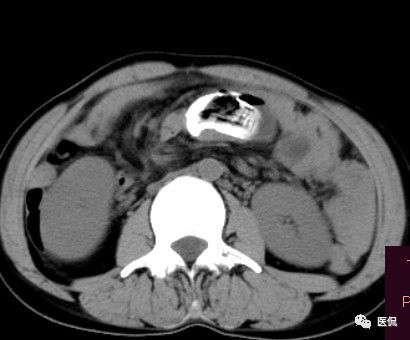

女 40岁 ,10年前做个剖腹产术。之后到现在一直感觉肚子疼,去很多医院做检查 诊断肠结核,经过反复抗结核治疗。病人10年瘦了几十斤。

腹腔内残留的纱布在人体内引起渗出或液化坏死并纤维包裹形成异物性脓肿(纱布瘤)。纱布瘤的影像特点:圆形或卵圆形肿块,较大,有完整包膜,薄壁,较少的情况下为厚壁,边界较完整,增强后薄膜可以持续强化。不同时期的纱布瘤可以有不同表现:早期(10个月或半年内)多表现为蜂窝状;2~5年内一般表现为囊性飘带状;10~20年之后则为实性软组织密度,包膜钙化呈钙化网状结构。手术过程中残留在人体内的医用纱布所形成的肿瘤样病变。

手术所见:腹腔内无腹水,肿块位于右上腹,约15x10x8cm大小 ,周围网膜包裹粘连,向胆囊三角处延续,呈囊性,与周围结构无明显浸润,仔细分离粘连,逐步游离暴露肿块,见肿块与右肾及结肠、十二指肠无明显关系,初步确定为肿大的胆囊,继续向肝门部游离,见肿块与胃窦粘连,因分离困难,决定切开肿块。穿刺肿块有黄色脓液抽出,考虑胆囊脓肿,切开囊壁,吸出大量黄色混浊脓液约1200ml,探查囊腔,见粘膜层为胆囊粘膜,腔内有一异物残留,经证实为医用盐水纱布,取出纱布约15x15cm大小,封存。继续游离胆囊至完整切除,检查囊壁无明显占位病变。

病理诊断:胆囊异物残留,胆囊化脓性炎、胆囊脓肿。

纱布团遗留腹腔后,首先由大网膜及邻近肠管将其紧密粘连并包裹,自肠管与纱布团粘连处开始逐渐向周围扩展产生纤维结缔组织包膜直至完全包住纱布团,该包膜血管丰富,充血明显,随时间延长逐渐向纱布团网眼内生长,使包膜逐渐增厚。机体还通过在包膜内产生大量异物巨细胞来围歼异物纱线,使包膜内侧形成脓肿。当包膜完全形成后,肠管与纱布团的粘连变的疏松,此时纱布团具有了一定的活动度。

腹腔内遗留纱布团的影像学表现,以B超较具特征性,其主要表现为:腹腔或盆腔内特殊率减的黑色包块,后方伴有扇形衰减的声影,上窄下宽,好似一“黑色大布”,早期包块内含有不规则光团或光点,随时间延长有缩小或消失,为纱布团内气体。CT的优势在于早期常表现为软组织密度的肿块,其内可见多少不等的气泡,随时间的延长气泡逐渐被吸收减少至消失,增强扫描可见包膜不同程度强化而内容物无强化。熟悉其影像学表现,可在术前作出明确诊断。